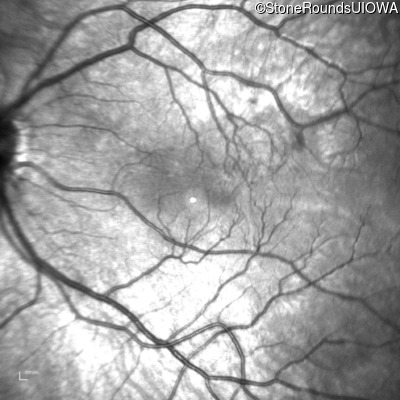

Infrared Fundus Photograph - Right - 20/2000

Exemplar